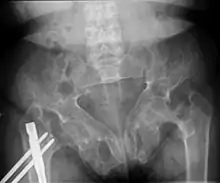

Brown tumors in the pelvis and a hip fracture.[18]

Renal osteodystrophy is usually diagnosed after treatment for end-stage kidney disease begins; however the CKD-MBD starts early in the course of CKD.[1][6] In advanced stages, blood tests will indicate decreased calcium and calcitriol (vitamin D) and increased phosphate, and parathyroid hormone levels. In earlier stages, serum calcium, phosphate levels are normal at the expense of high parathyroid hormone and fibroblast growth factor-23 levels. X-rays will also show bone features of renal osteodystrophy (subperiostic bone resorption, chondrocalcinosis at the knees and pubic symphysis, osteopenia and bone fractures) but may be difficult to differentiate from other conditions. Since the diagnosis of these bone abnormalities cannot be obtained correctly by current clinical, biochemical, and imaging methods (including measurement of bone-mineral density), bone biopsy has been, and still remains, the gold standard analysis for assessing the exact type of renal osteodystrophy.[6][16]